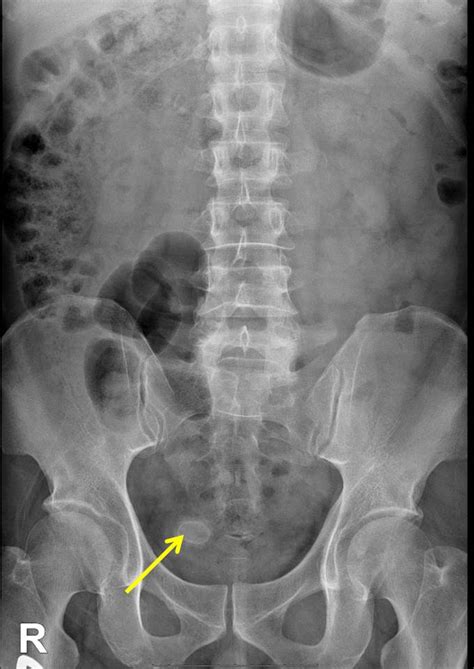

• Ultrasound: This is often the first test used to look for gallstones. It’s non-invasive and can provide clear images of the gallbladder and surrounding structures.